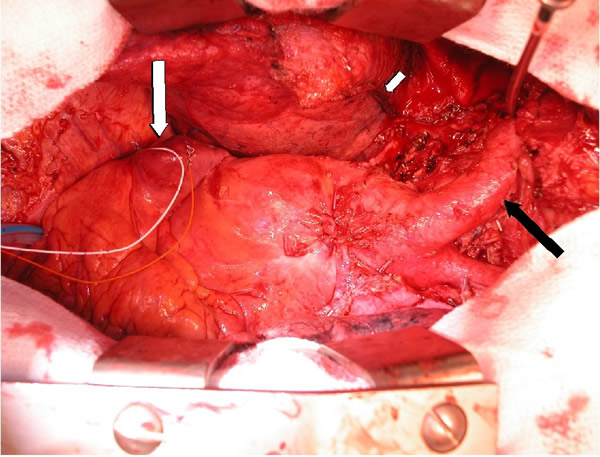

The patient was taken to the operating room and sternotomy performed after division of several large collateral chest wall veins. The pericardium was opened and resection of all thymic tissue was undertaken starting at the diaphragm (Figure 3). The SVC was transected at the confluence of the right subclavian and jugular veins and found to be filled with fibrotic tissue (Figure 4A). Frozen section examination of the luminal contents identified benign fibrotic tissue. The SVC was mobilized to the level of the right atrium en-bloc with the tumor, the azygos vein was divided, and a wedge resection of the medial aspect of the right upper lobe was performed. At this point, the tumor had been completely mobilized except for an intravascular extension through the SVC into the right atrium (Figure 4B).

The patient was placed on cardiopulmonary bypass via the aorta and inferior vena cava. The SVC was resected with the atrium and the tumor removed en-bloc (Figures 5-7). The atrium was closed and the patient weaned off cardiopulmonary bypass. The patient was extubated on postoperative day 2 and discharged home on postoperative day 7. Final pathology revealed a malignant thymoma with vascular and lung invasion.